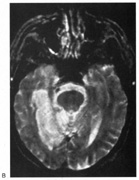

Fig. 10. Striate quadrantanopia. A. A 68-year-old woman with a stroke 3 years previously, causing left inferior quadrantanopia. B. MRI shows infarct of the superior bank of the right calcarine cortex.

The upper and lower banks can also be involved separately. Ischemia can do this because the banks have separate blood supplies. Upper bank infarcts cause homonymous contralateral inferior quadrantanopia (Fig. 10) and lower bank infarcts cause superior quadrantanopia. Although altitudinal defects have been reported occasionally,47,48 most quadrantic defects do not align at the horizontal meridian, because the upper field merges without interruption into the lower field in the depths of the calcarine fissure. Thus it has been argued that quadrantic defects that respect the horizontal meridian are caused by involvement of area V2, surrounding striate cortex,49 which remains controversial. Quadrantanopias are three times more common with striate lesions than with optic radiation lesions.33 Striate quadrantanopias are more frequently isolated signs but can be associated with other signs of higher cortical visual dysfunction, such as pure alexia or hemiachromatopsia, whereas optic radiation quadrantanopias usually are accompanied by hemiparesis, dysphasia, or amnestic problems.33